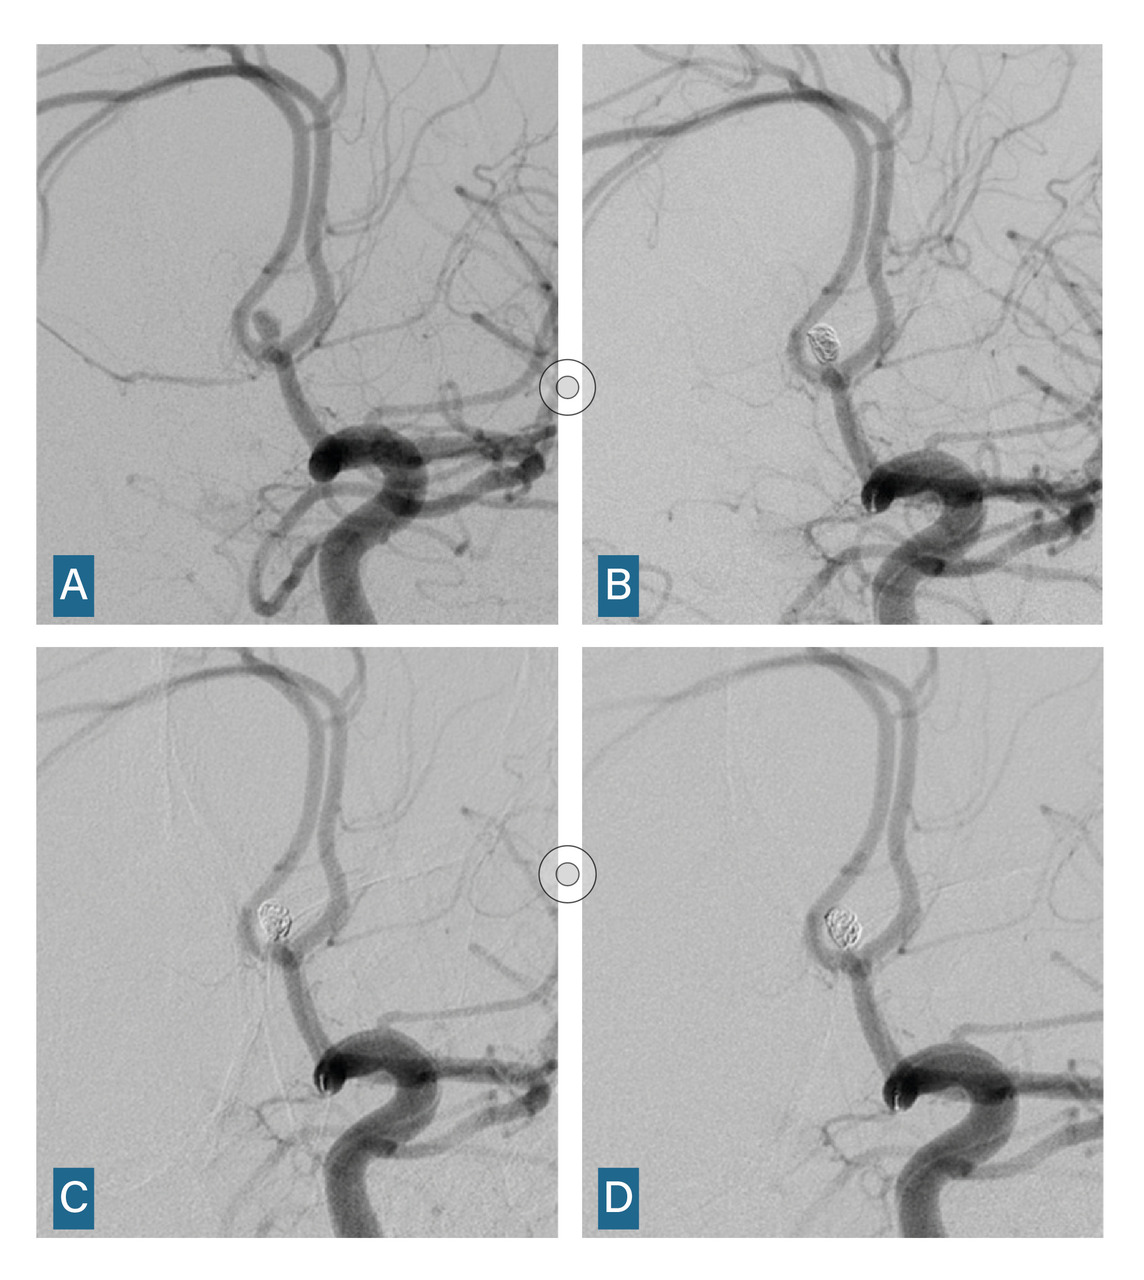

L’angiographie digitale permet de planifier et de suivre le traitement lorsqu’il est réalisé par voie endovasculaire. (fig. 4)